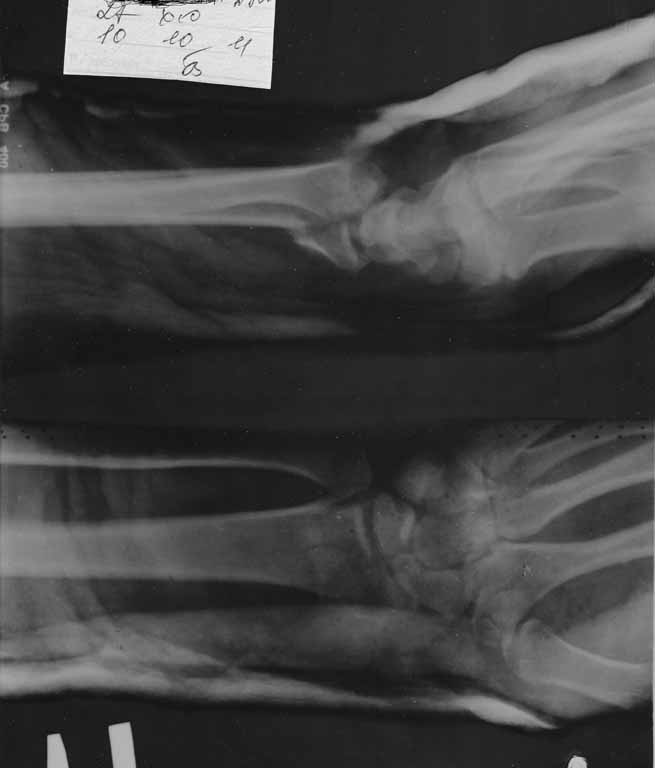

Давность травмы- неделя.

Интересует доступ, рекомендуемые фиксаторы.

Если есть,то примеры на снимках.